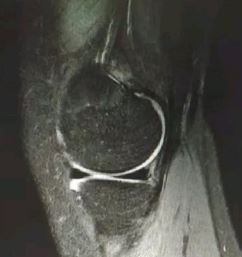

3级(III级):半月板内的高信号达到半月板的关节面,通常代表半月板撕裂。

(III级:半月板线性高信号,达关节面,与关节相同)